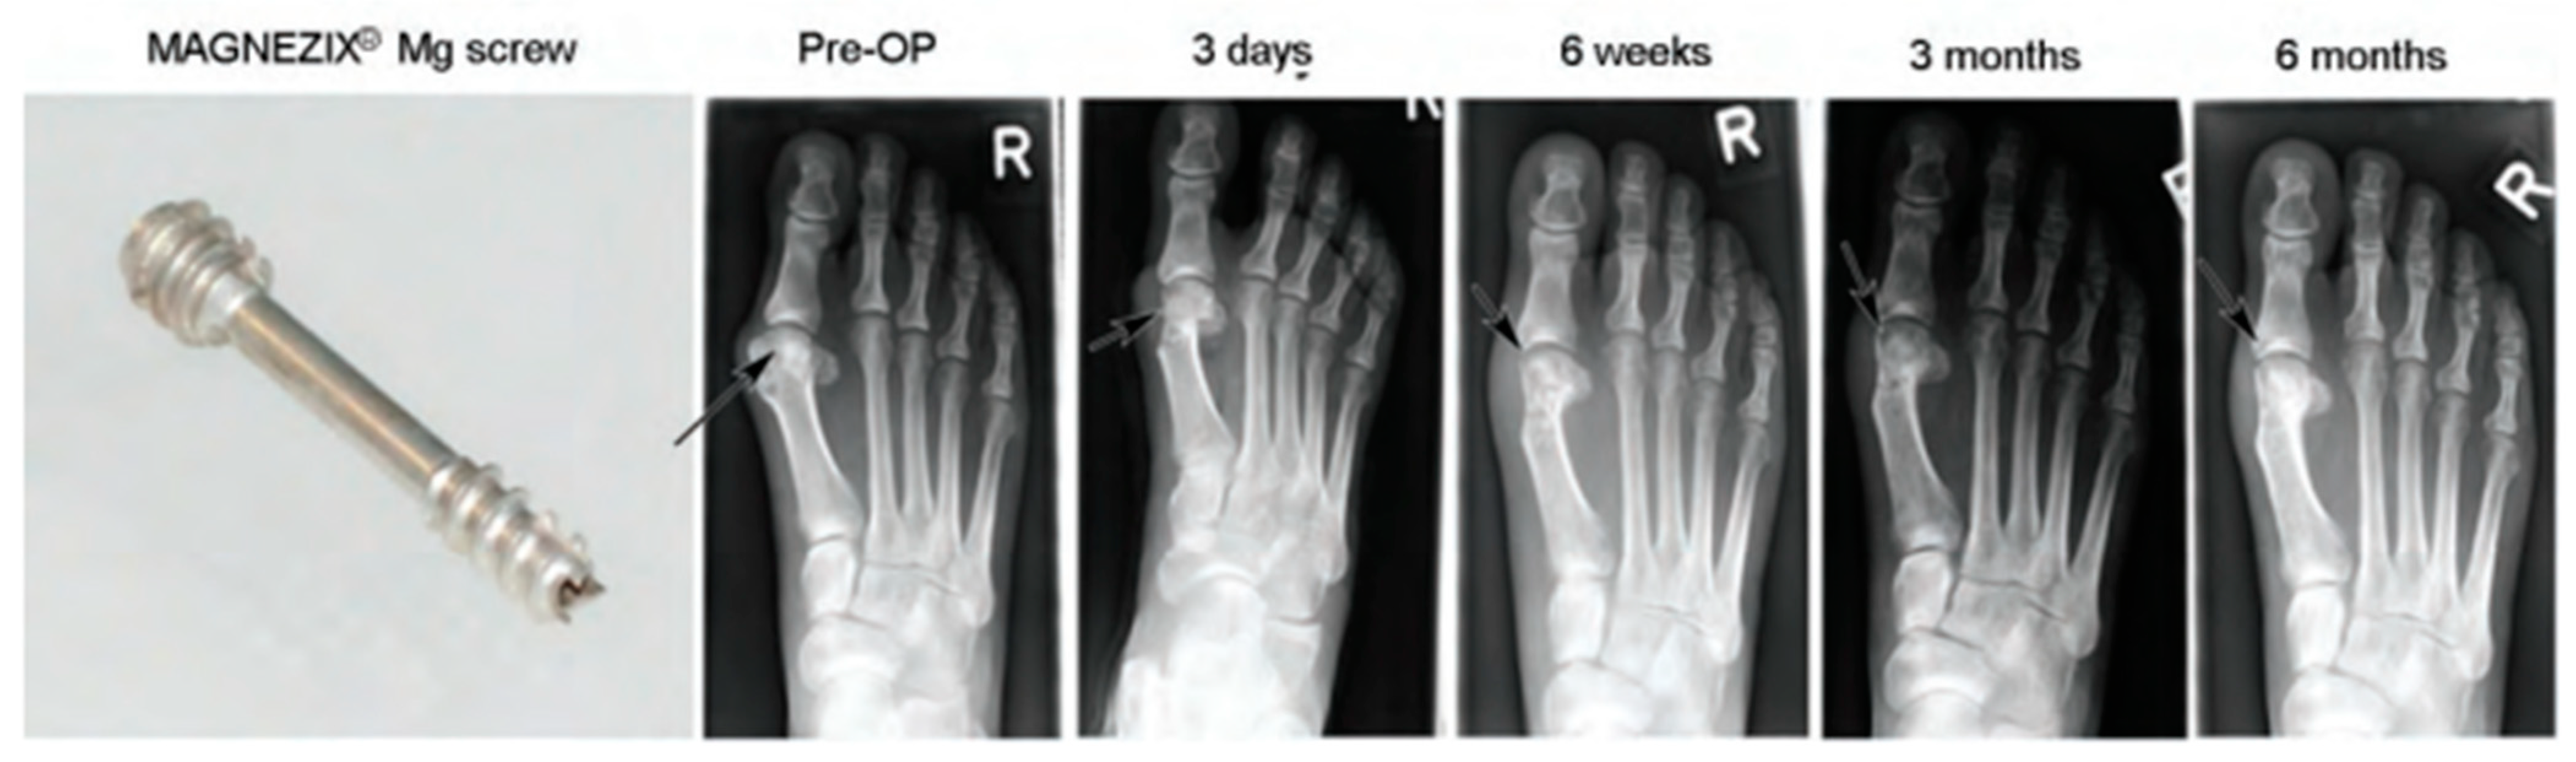

- Windhagen, H.; Radtke, K.; Weizbauer, A.; Diekmann, J.; Noll, Y.; Kreimeyer, U.; Schavan, R.; Stukenborg-Colsman, C.; Waizy, H. Biodegradable Magnesium-Based Screw Clinically Equivalent to Titanium Screw in Hallux Valgus Surgery: Short Term Results of the First Prospective, Randomized, Controlled Clinical Pilot Study. Biomed. Eng. Online 2013, 12, 62. [Google Scholar] [CrossRef] [PubMed]

- Plaass, C.; Ettinger, S.; Sonnow, L.; Koenneker, S.; Noll, Y.; Weizbauer, A.; Reifenrath, J.; Claassen, L.; Daniilidis, K.; Stukenborg-Colsman, C.; et al. Early Results Using a Biodegradable Magnesium Screw for Modified Chevron Osteotomies. J. Orthop. Res. 2016, 34, 2207–2214. [Google Scholar] [CrossRef]

- Plaass, C.; von Falck, C.; Ettinger, S.; Sonnow, L.; Calderone, F.; Weizbauer, A.; Reifenrath, J.; Claassen, L.; Waizy, H.; Daniilidis, K.; et al. Bioabsorbable Magnesium versus Standard Titanium Compression Screws for Fixation of Distal Metatarsal Osteotomies—3 Year Results of a Randomized Clinical Trial. J. Orthop. Sci. 2018, 23, 321–327. [Google Scholar] [CrossRef]

| Mg-Y-RE-Zr screws | Bunion correction | 13 | Germany | All healed | [202] |

| Mg-Y-RE-Zr screws | Bunion orthopaedics | 40 | Germany | 79% healing after 6 weeks, 90% healing after 12 weeks | [202] |

| Mg-Y-RE-Zr screws | Bunion orthopaedics | 100 | Germany | All healed | [202] |